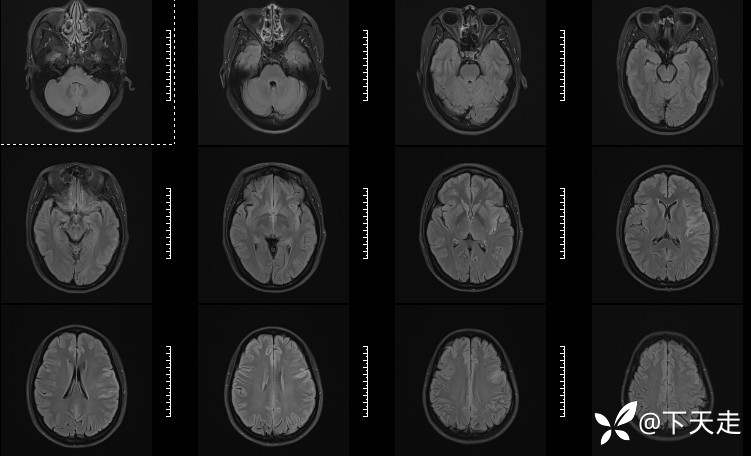

青鹊词 推荐青年女性,37岁,因不能言语就诊于耳鼻喉科,耳鼻喉科医生诊疗后建议神经内科就诊。

查体:神清,完全性运动性失语,四肢肌张力正常,肌力5级。

相关检验检查资料如下